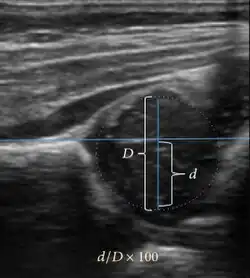

Ultrasound allows categorizing pediatric hips, according to Graf’s criteria, in four main types: normal, immature, and dysplastic (subluxed and dislocated). This classification is based on measurements of the acetabular inclination angle (alpha), cartilage roof angle (beta), and infant age. The femoral head coverage can also be determined by dividing the length of the femoral head covered by the acetabular fossa and the diameter of the femoral head. Its lower normal limits are 47% for boys and 44% for girls (Figure 11).[1]

Figure 11: